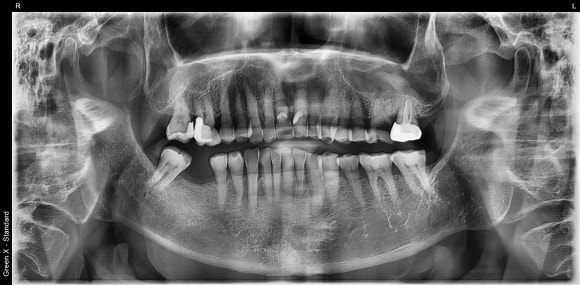

20241026

오른쪽 아래 어금니가 빠진지 여러 해가 되어

앞 뒤 치아들이 조금씩 빈공간을 향해 쓰러졌습니다.

그 탓에 어금니가 있었던 공간이 점점 좁아졌지요.

공간이 좁으면 좁은대로, 넓으면 넓은대로

정확한 위치에 정확한 각도로 식립한다면

임플란트 치료는 얼마든지 가능합니다.